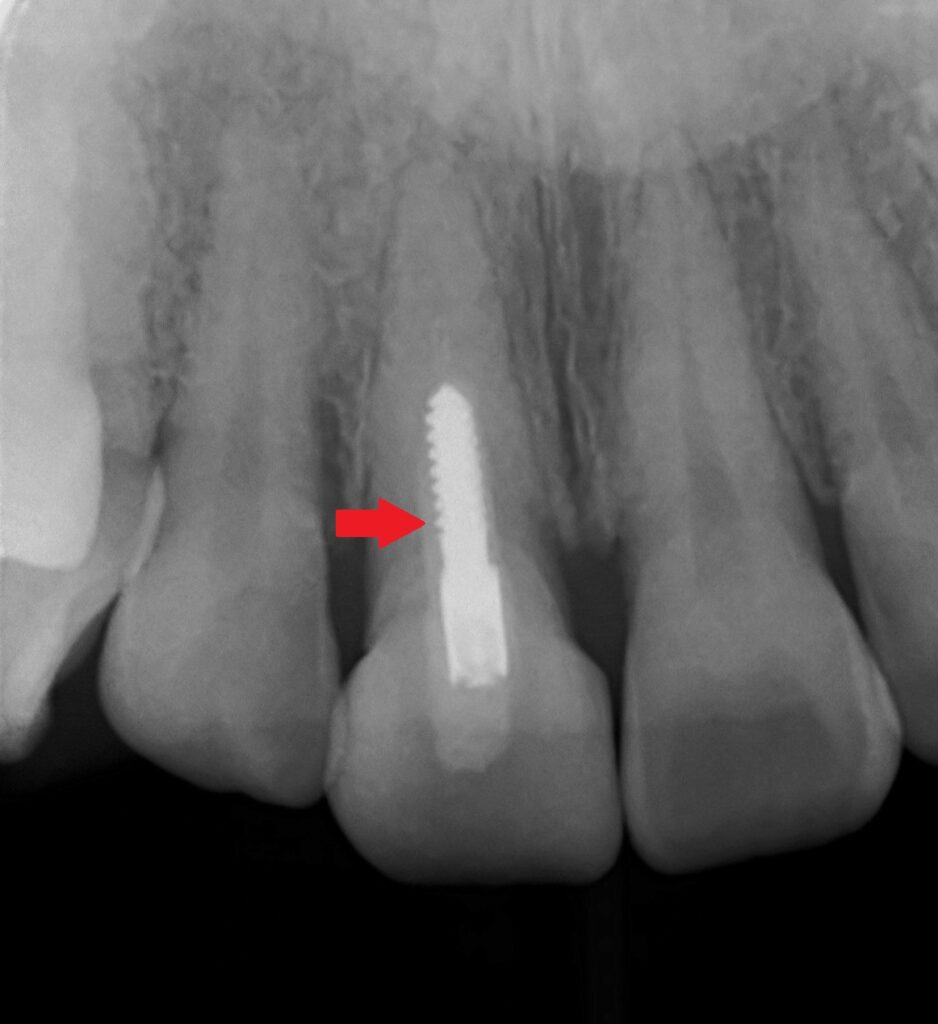

レントゲン写真(エックス線検査)で歯の中の状態を確認してみましょう。

今回の歯の内部が確認できます。

すぐに分かるのが、歯の中にネジ?のような金属が埋め込まれています。

これはスクリューピンと言って、神経を取った歯の土台として使用します。

またかぶせ物(クラウン)は金属を使用していない事も分かるので、黒く見える原因は、かぶせ物の影響やメタルタトゥーでは無い事が分かります。

今回の根元の黒い原因は、かぶせてある歯の内部が変色して黒く見えているのだと推測されます。

先ほどの①の歯が原因で黒く見えている状態ですね。